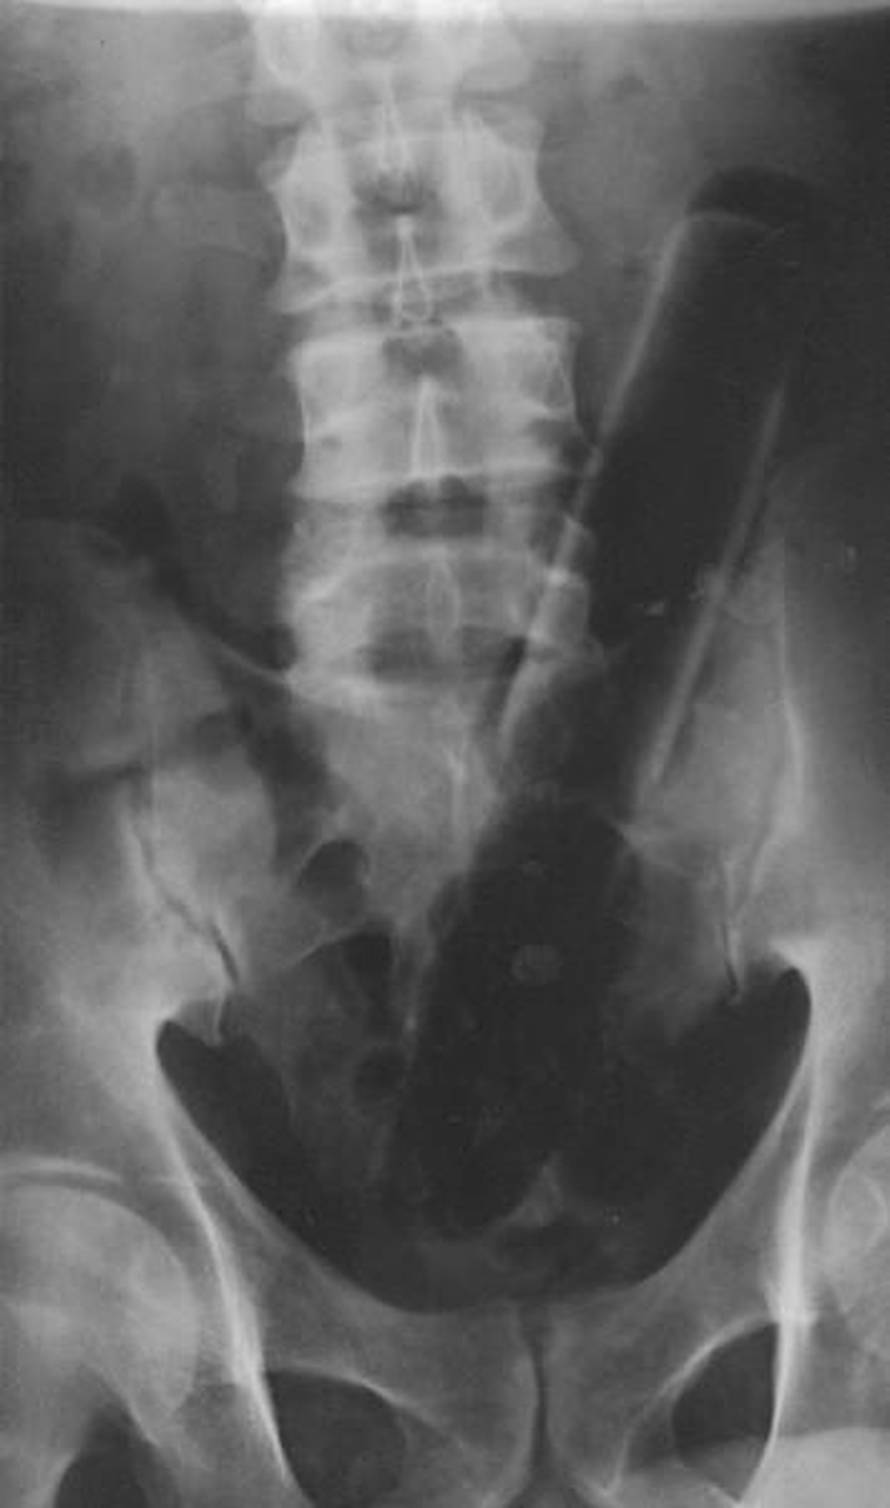

BIZARNE IGRICE: Kirurzi Kliničke bolnice Merkur u Zagrebu iz anusa maštovitih pacijenata moraju vaditi predmete koji 'pobjegnu' tijekom 'igrica'